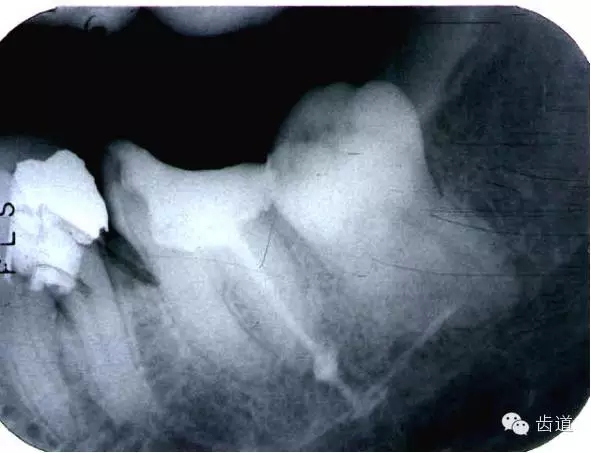

左上4鑄造樁側(cè)穿